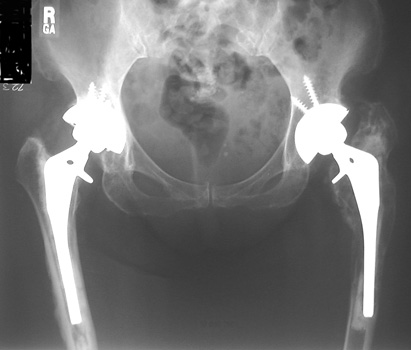

LooseningAs pain and disability due to loosening become severe enough to require revision arthroplasty, abnormalities in the binding of the cement to the bone or prosthesis are almost always visible radiographically. Radiographic abnormalities include:

LOOSENING WITH FEMORAL COMPONENT IN VARUS LOOSENING

SUBSIDENCE - loose femoral prosthesis with interface widening,

osteolysis Gruen zone 6, cement fracture left femoral component

and osteolysis, with femoral component in valgus.